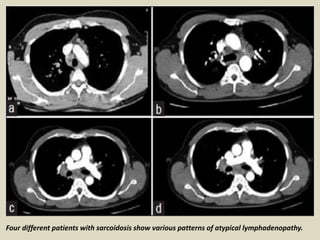

Atypical patterns: Atypical patterns of lymphadenopathy

occur more frequently in patients older than 50 years. Lymph

nodes enlargement may be asymmetric or show unusual

locations (i.e., internal mammary chain, paravertebral or rtero-

crural regions). Such findings should lead to the inclusion of

entities such as lymphoma or tuberculosis in the differential

diagnosis. Isolated unilateral hilar lymph nodes enlargement,

usually on the right side, is seen in less than 5% of cases.

Enlargement of mediastinal lymph nodes without hilar lymph

nodes enlargement is even less common. The enlarged nodes

may occasionally become calcified, this being related to the

duration of the disease (calcification occurs in 3% of patients

after 5 years and in 20% after 10 years). The calcifications in

sarcoidosis may be indistinguishable from those seen in

tuberculosis and histoplasmosis. Eggshell-like calcifications

may also be identified in silicosis.

Four different patients with sarcoidosis show various patterns of atypical lymphadenopathy.